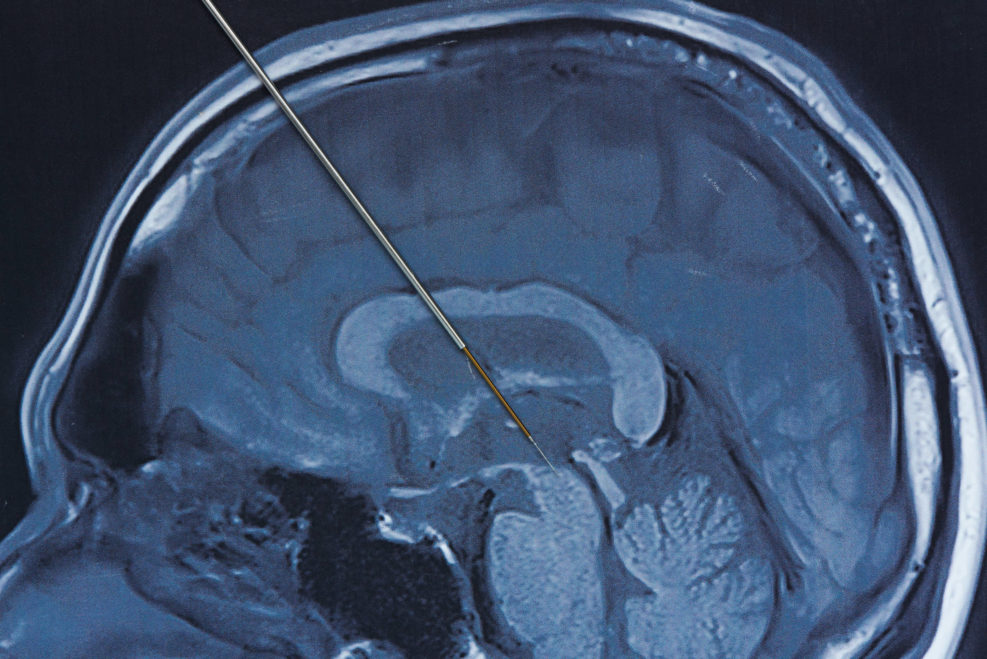

Part 3: Can quantum mechanics help decipher consciousness? Free will? Nobel laureate Roger Penrose, among others, looked to the quantum world for models. Angus Menuge thinks that physicists John von Neumann’s and Henry Stapp’s models of quantum mechanics provide some directions.